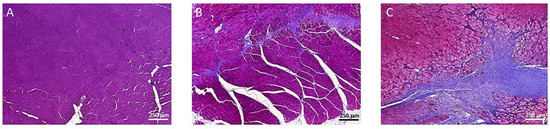

3.3. Muscle Fibrosis